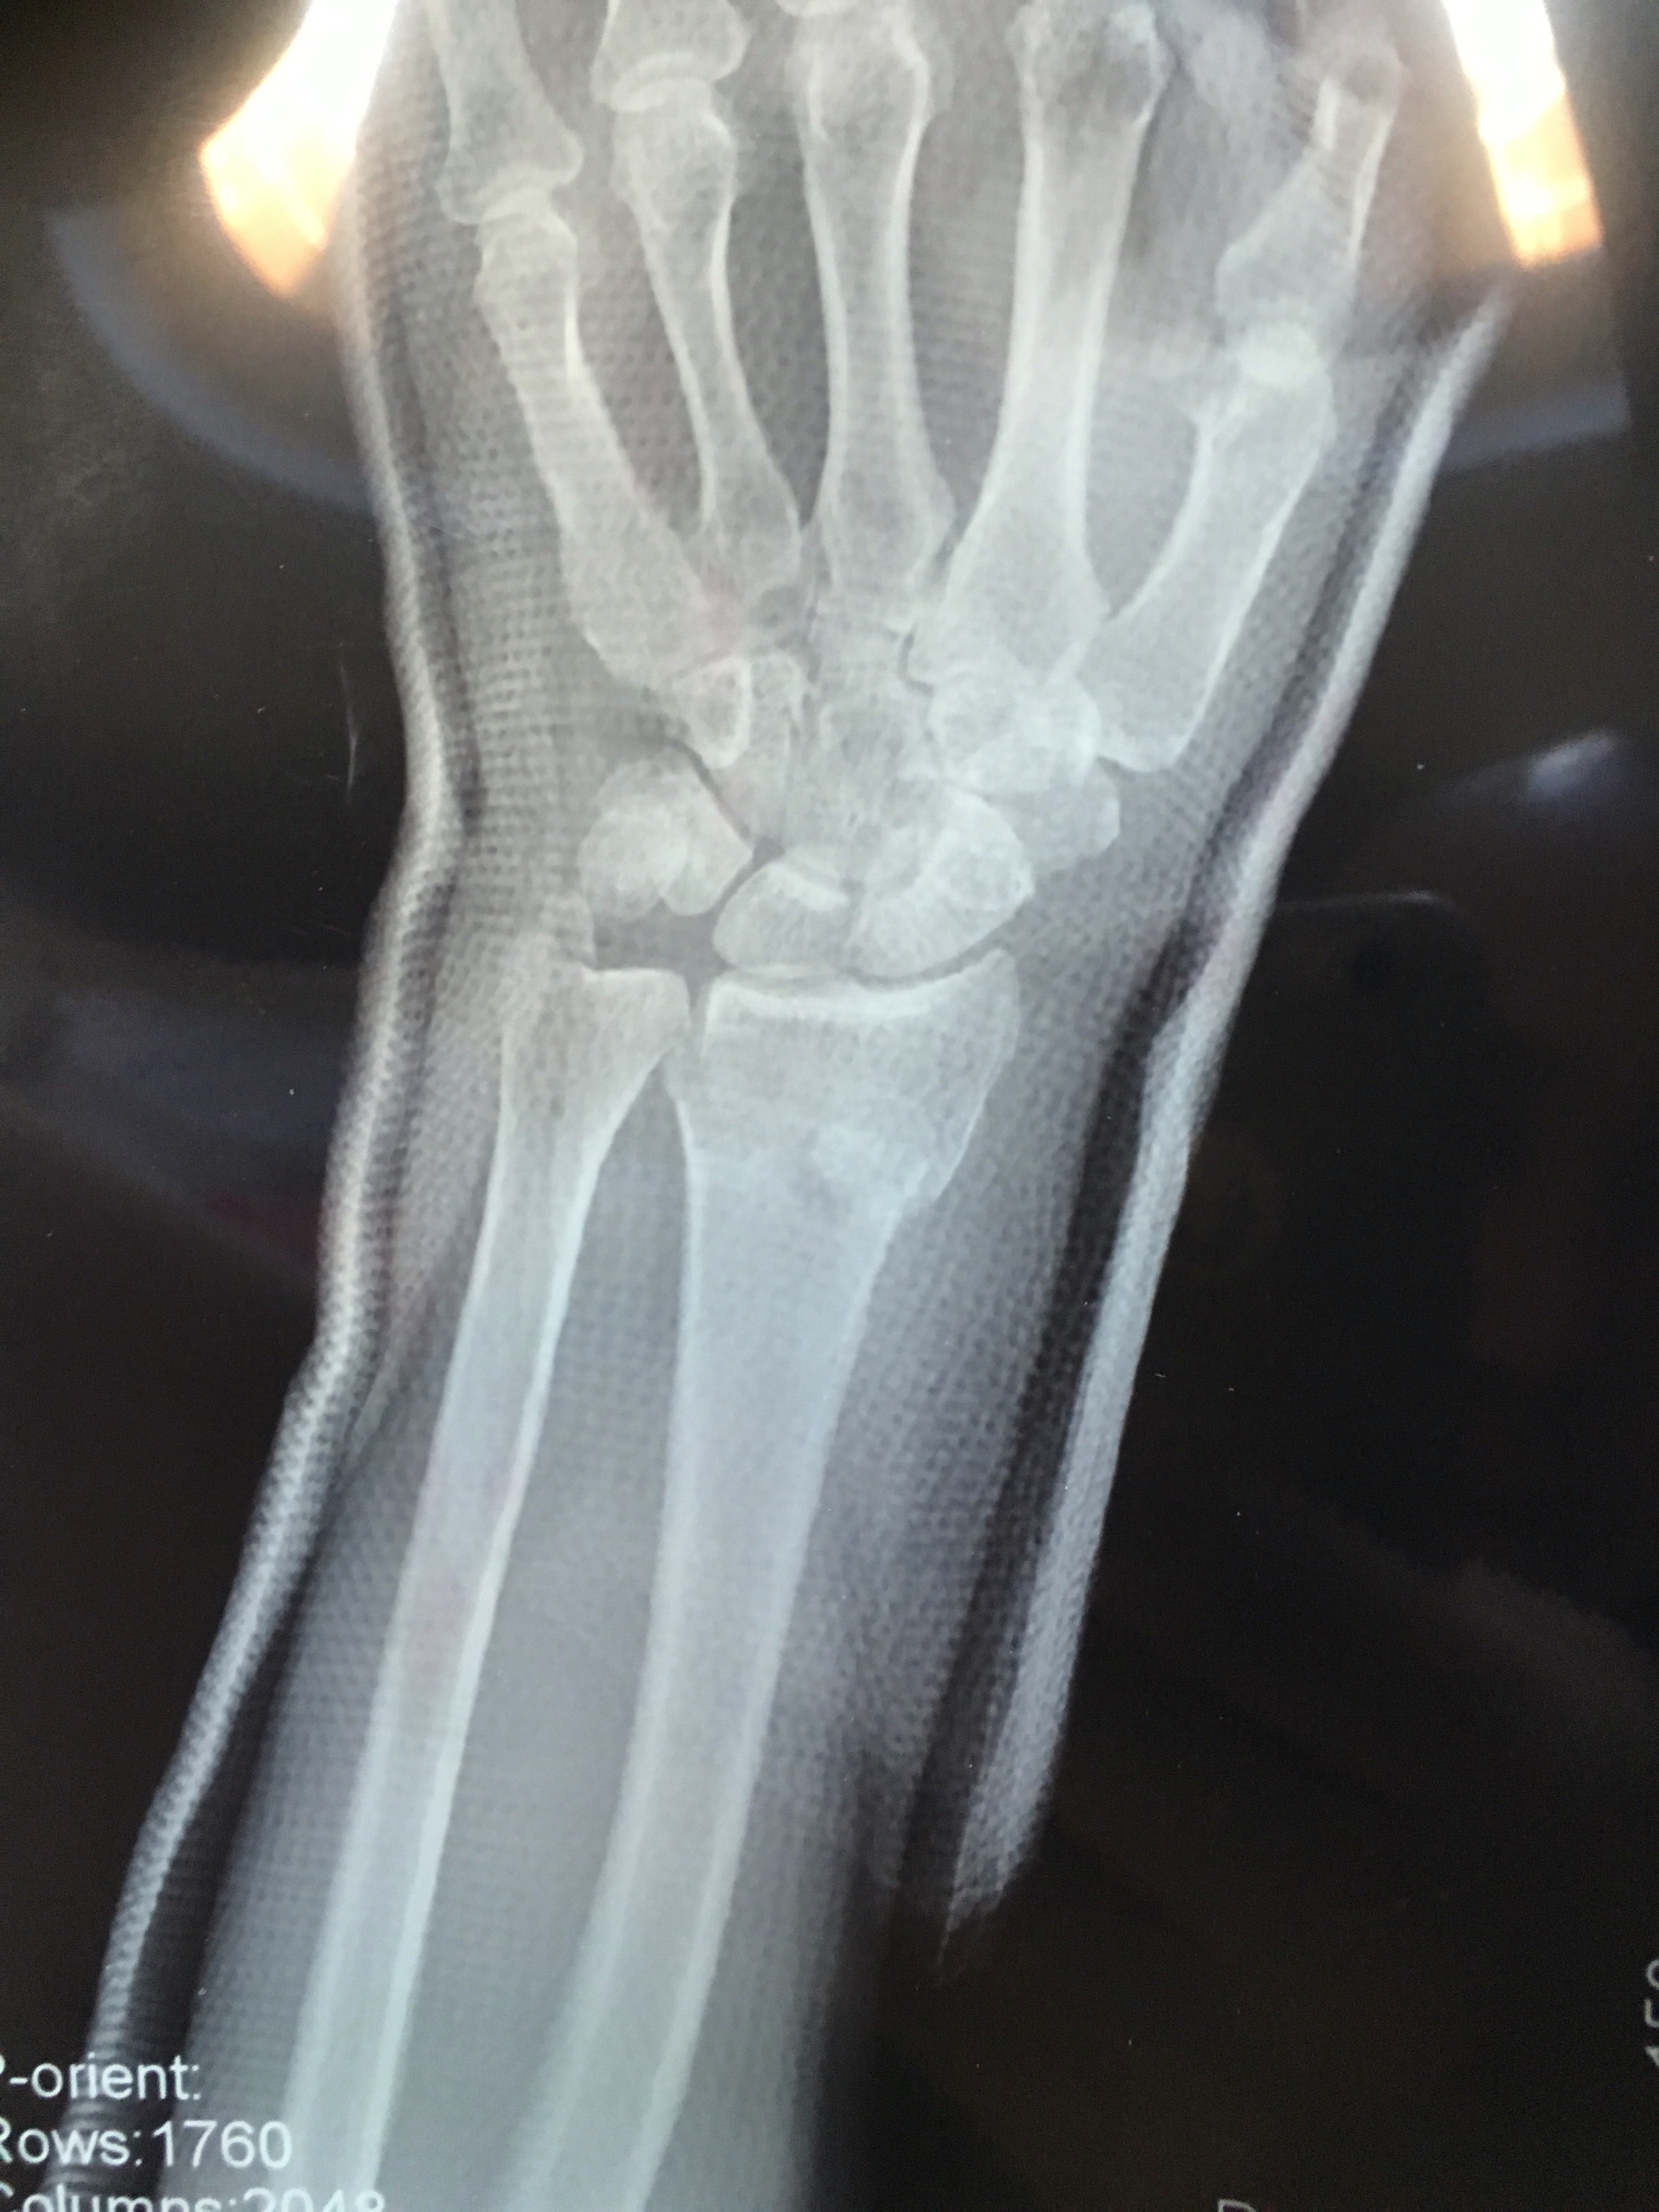

求助 求大神帮忙看看复位的怎么样?

可以保守治疗吗?

换家医院看看